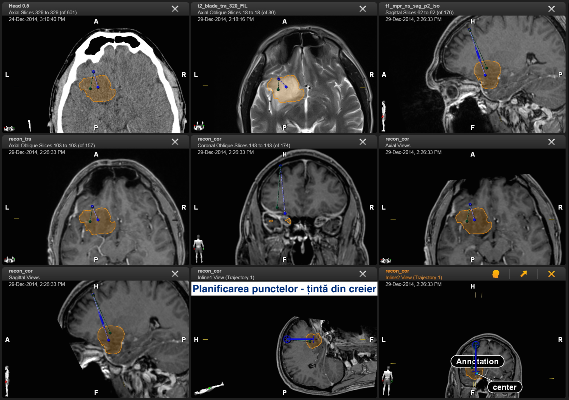

Toate aceste incomodități lipsesc în cadrul biopsiei cu utilizarea neuronavigației fără cadru stereotaxic. Astfel, procedura pentru pacient arată cât se poate de simplu. Pacientul intră în sala de operație fără cadru pe cap și iese de acolo cu procedura de biopsie realizată, localizarea și precizia biopsiei fiind confirmate pe masa de operație.

Biopsia cerebrală reprezintă o tehnică indispensabilă pentru pacienții neurochirurgicali care suferă de o patologie a creierului greu accesibilă. Metoda este absolut necesară ca etapă premergătoare, în cazul localizării proceselor patologice în zone elocvente ale creierului sau în cazul în care este nevoie de un diagnostic diferențial precis. Utilizarea sistemului nu este limitată numai la biopsie. Sistemul de neuronavigație existent în SCR permite a ghida nu numai canulele de biopsie dar și alte instrumente, în special, endoscoapele cerebrale. Acest lucru permite de a accesa într-o manieră sigură orice proces localizat în creier, iar etapa curativă sau de diagnostic poate fi realizată prin control vizual, cu ajutorul endoscopului cerebral.

Pacientul S., a beneficiat de tehnologiile existente în volum deplin. Operația a durat 2 ore. Pacientul și-a revenit după o oră de la intervenția chirurgicală, iar peste o zi a fost externat. Pentru prelevarea biopsiei a fost aleasă o porțiune de tumoare localizată la adâncimea de 13 cm de la suprafață. Locul ales a fost țintit cu precizia de 0,2mm! Acest grad de precizie este suficient pentru toate biopsiile cerebrale, iar în anumite circumstanțe, sistemul poate fi utilizat și pentru tratamentul parkinsonismului.